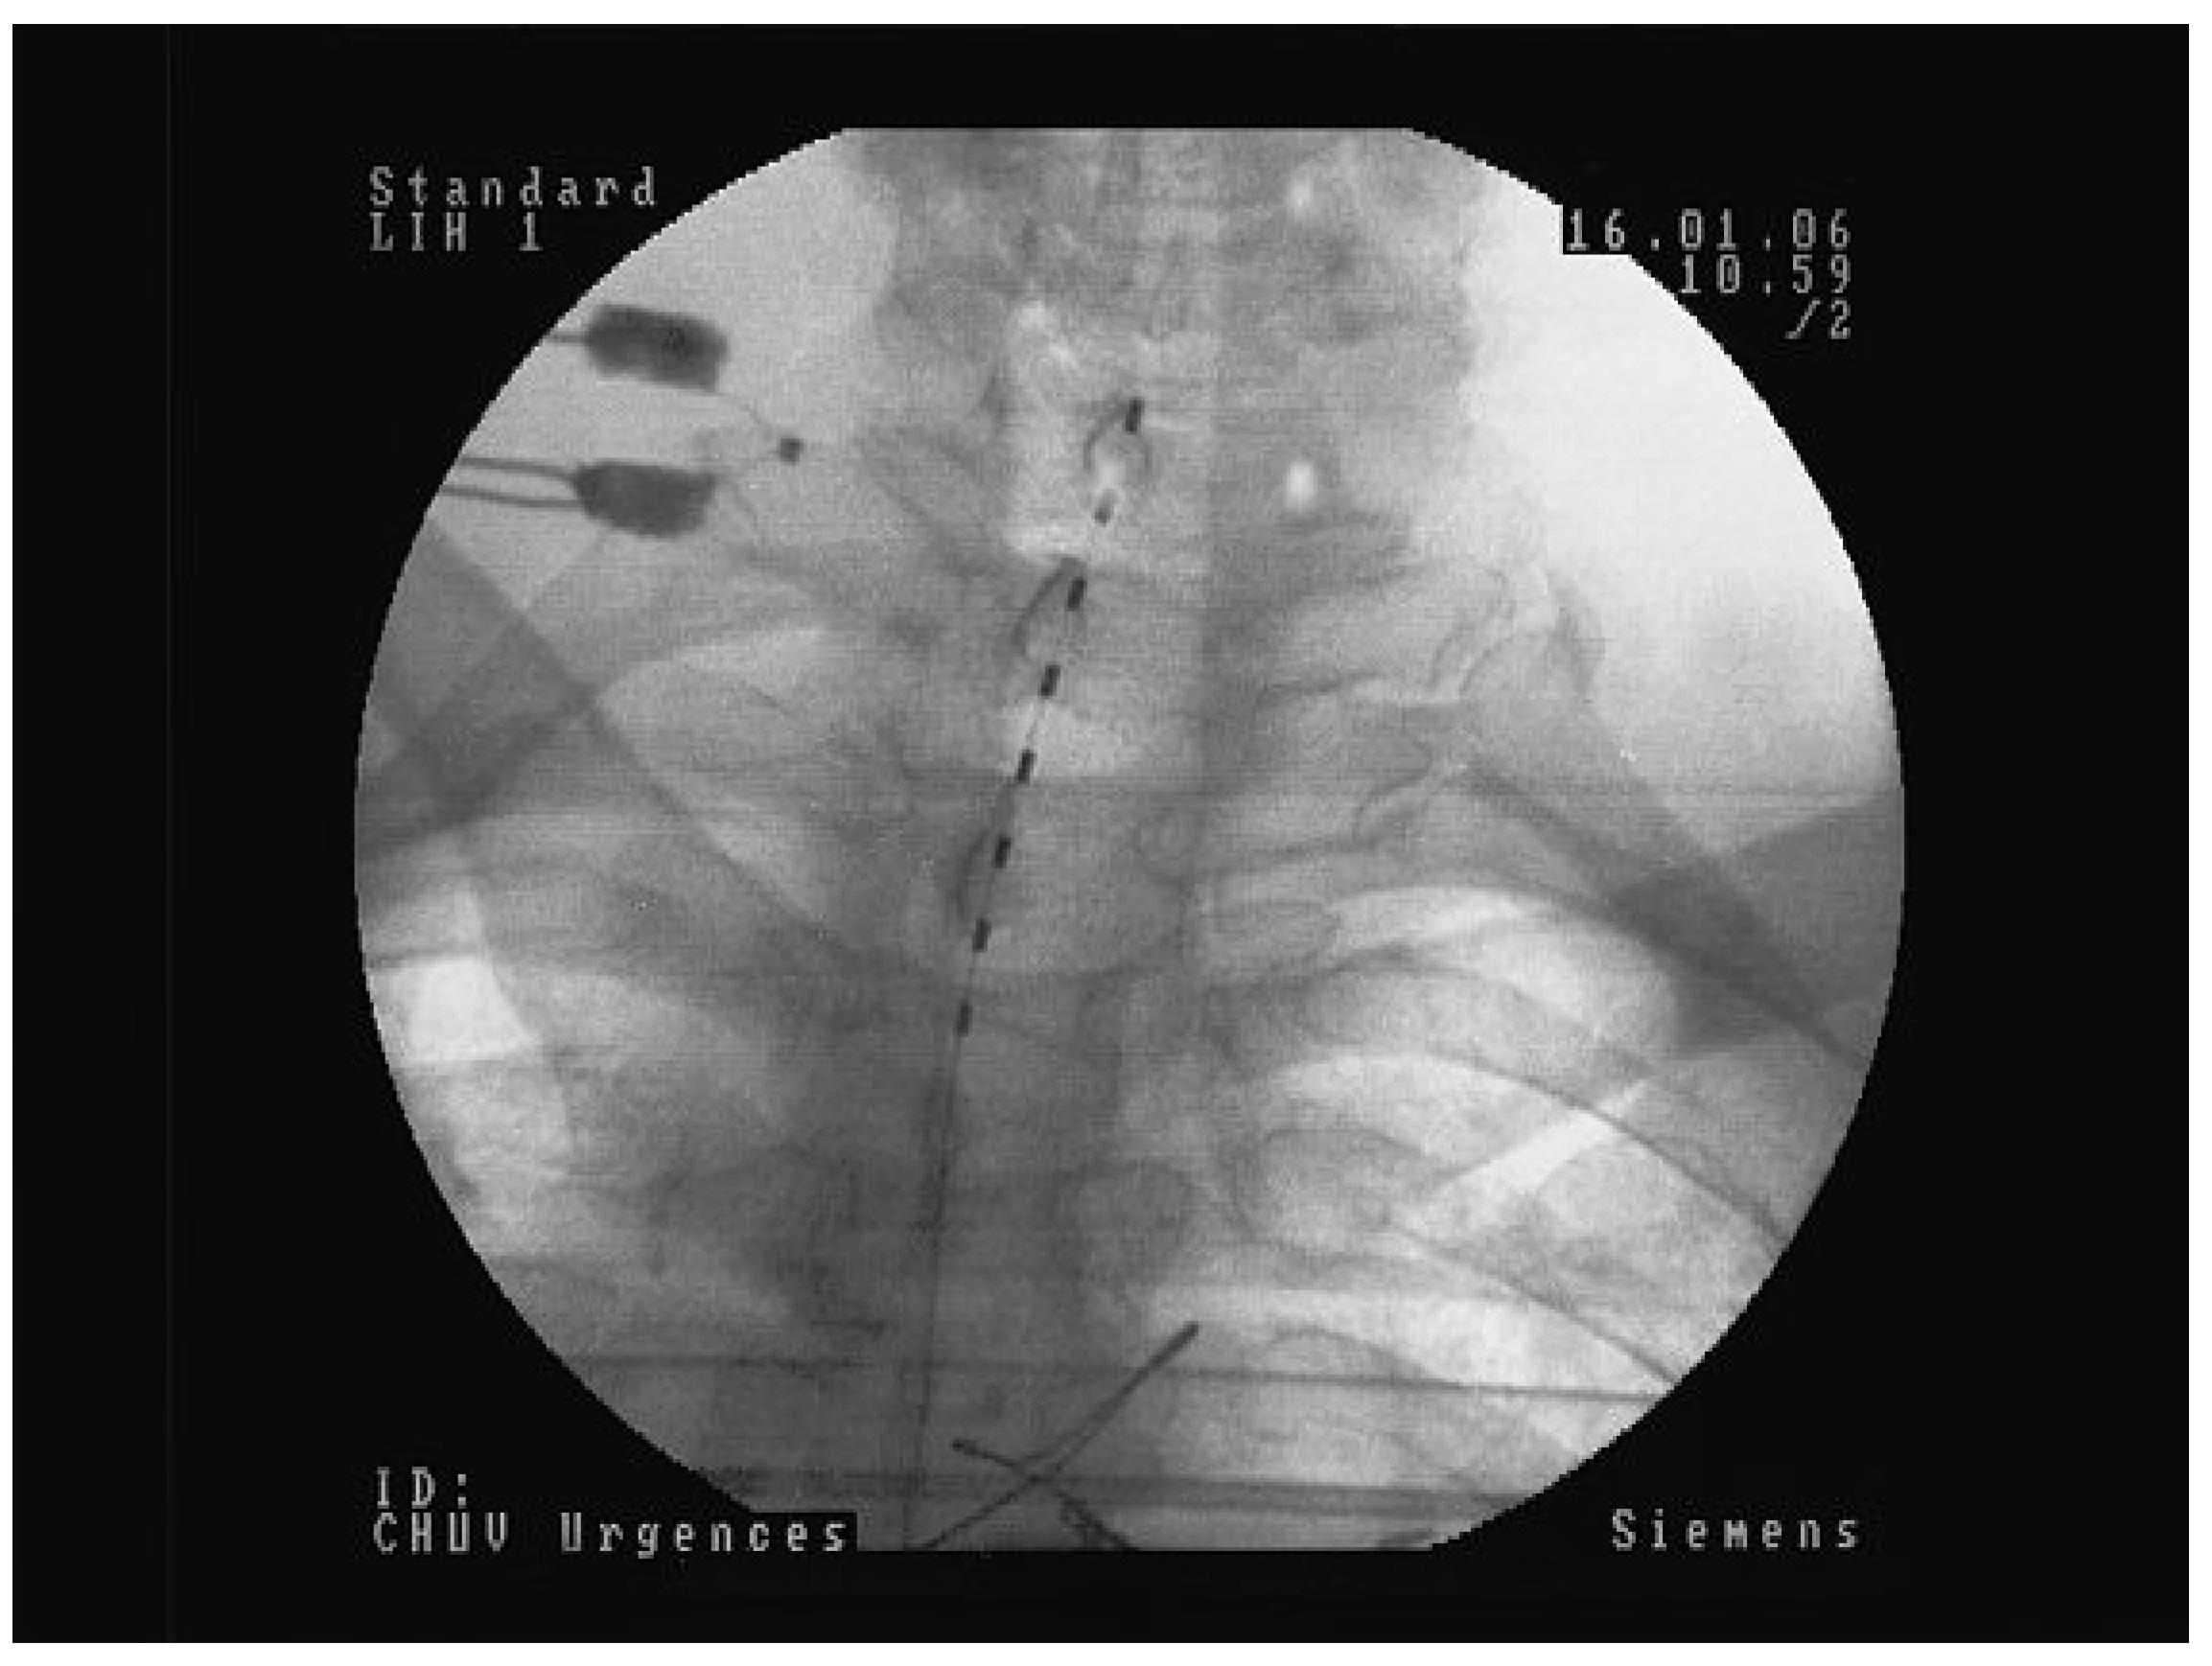

![]() |